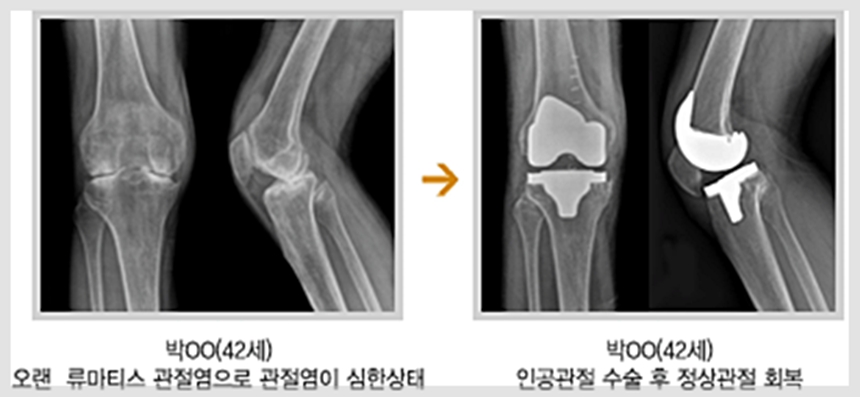

5. 실제 사례 & 따뜻한 후기들 💖

누군가의 삶을 바꾼 이야기 📝